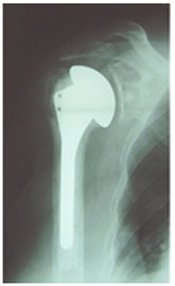

shoulder reverse shoulder replacement

X-ray of a reverse shoulder replacement

Stemmed shoulder replacement

X-ray of shoulder demonstrating a stemmed shoulder replacement